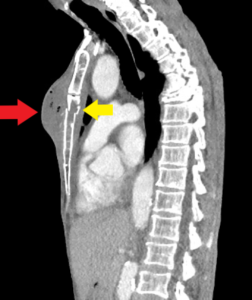

Chest wall abscess, CT sagittal, annotated. JETem 2024

Chest wall abscess CT sagittal annotated. JETem 2024